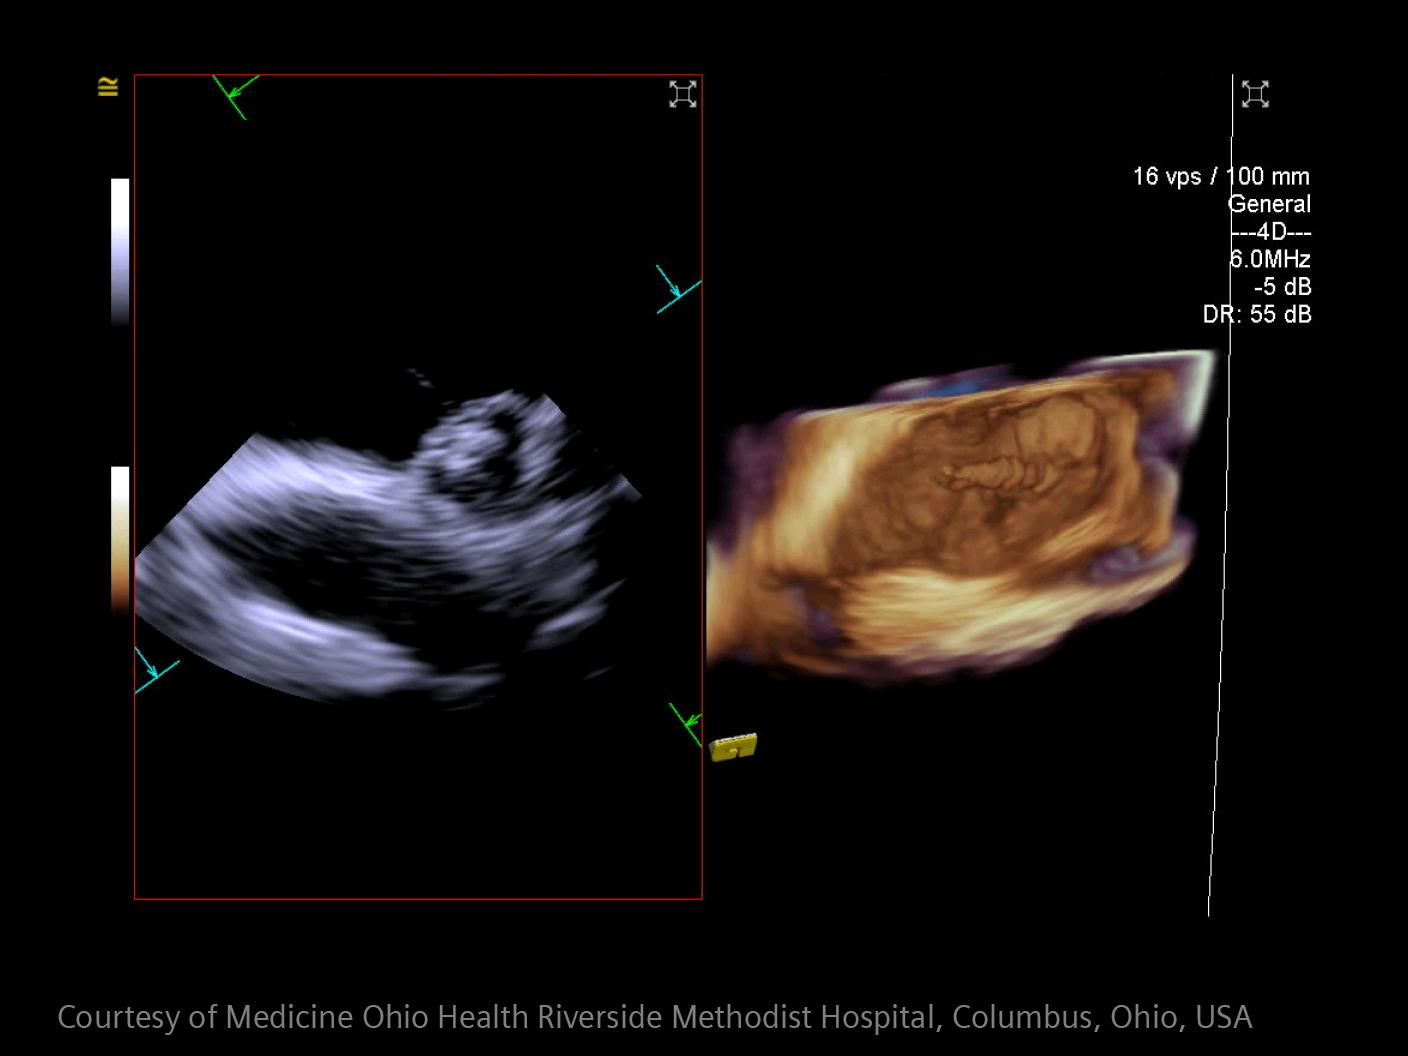

In stroke care, time is brain. Rapid and accurate imaging is crucial to assess the extent of brain injury and guide immediate treatment. Angiography, MRI, CT, ultrasound, and lab diagnostics are essential tools in identifying stroke type, location, and severity. Advances in imaging technology now allow for even faster acquisition, improved resolution, and enhanced visualization of brain tissue and blood vessels. Innovations such as perfusion imaging, real-time vascular mapping, and AI-assisted diagnostics are transforming stroke workflows and enabling precise, timely interventions.